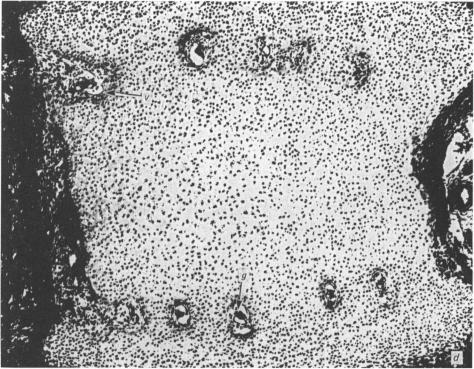

Bone formation in the vertebral centra commences within the centrum and is in this respect analogous to the secondary ossification which occurs in the epiphysis of a long bone. Bone tissue first appears at about the 85 mm C.R. stage and not in the 55 mm C.R. length embryo; at the latter stage blood vessels and calcification alone were observed. The connective tissue cells within the cartilage canal appear to assist osteogenesis by providing osteogenic cells which lay down bone in the walls of the cartilage canal, and provide cells which remove calcified cartilage found at the periphery of the canal; they assist growth by producing an appreciable number of chondrocytes that permit lateral expansion of the centra. Osteogenesis appears to occur in multiple foci within the growth plate of the older embryos and could account for the rapid rate of growth of vertebrae. Bone formation occurs in both mineralised and unmineralised matrix (as seen on the walls of the cartilage canals). The blood vessels within the growing vertebra tend to follow the zone of cartilage hypertrophy.